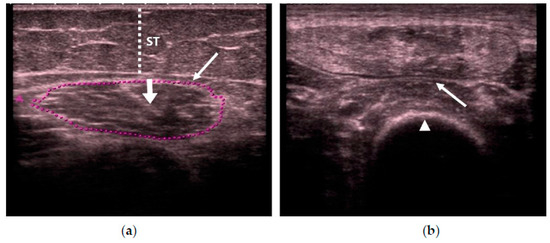

In all of the studies, we first used real-time B-mode US scanning to assess the muscle quality according to its echogenicity by using a specifically designed scale, due to the importance of age-related muscle replacement by fat and fibrous tissue or sarcopenia. The scale was as follows (see Figure 1): homogenous hypoechogenicity (Category 1) [18], heterogeneous hypoechogenicity (Category 2) [21], fat infiltration (Category 3) [22,23,24], and with fasciitis and/or necrosis (Category 4) [18,25]. We measured the intramuscular central tendon thickness in mm, with an insonation angle perpendicular to the tendon.

Figure 1.

Transversal ultrasonography (US) scan that shows quadriceps rectus femoris (QRF) muscle echogenicity. (a) Matched healthy control: Category 1 (normal hypoechogenicity), with the central tendon (thick arrow). (b) Category 2 (heterogeneous). (c) Category 3 (fat infiltration). (d) Category 4 (atrophy due to fasciitis and muscle necrosis). QRF: quadriceps rectus femoris (arrows); femur (arrowhead); ST: subcutaneous cellular tissue (dotted line); US: ultrasound.